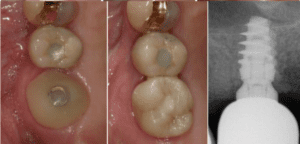

„Klinischer Stellenwert und Management der biologischen Breite am Implantat“